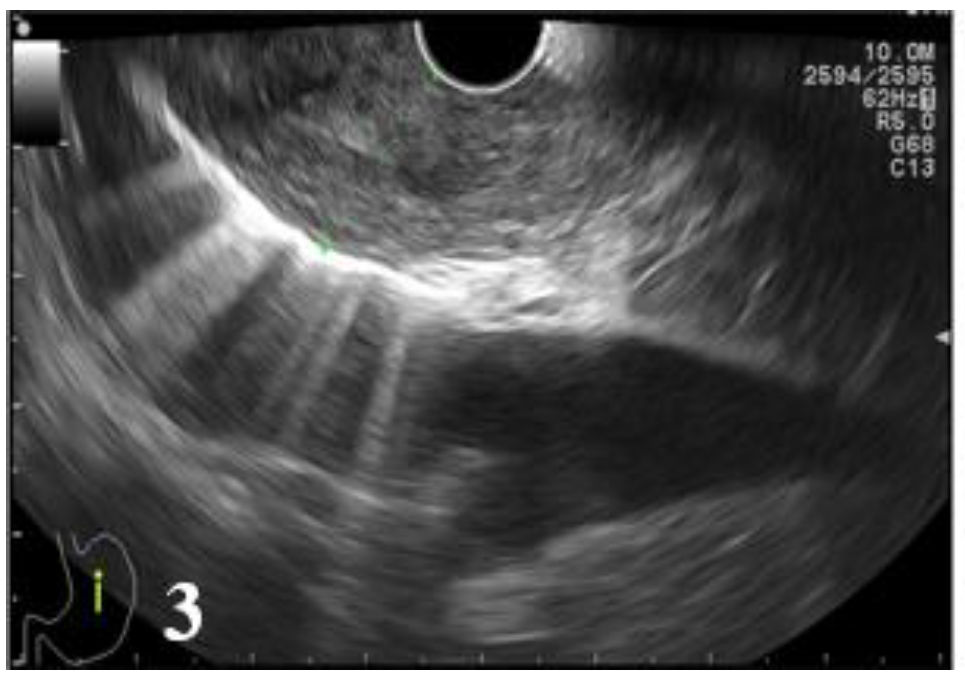

Figure 3.

EUS image showing the lesion that involves all the layers of the distal esophageal wall without invasion into the aorta (T3).